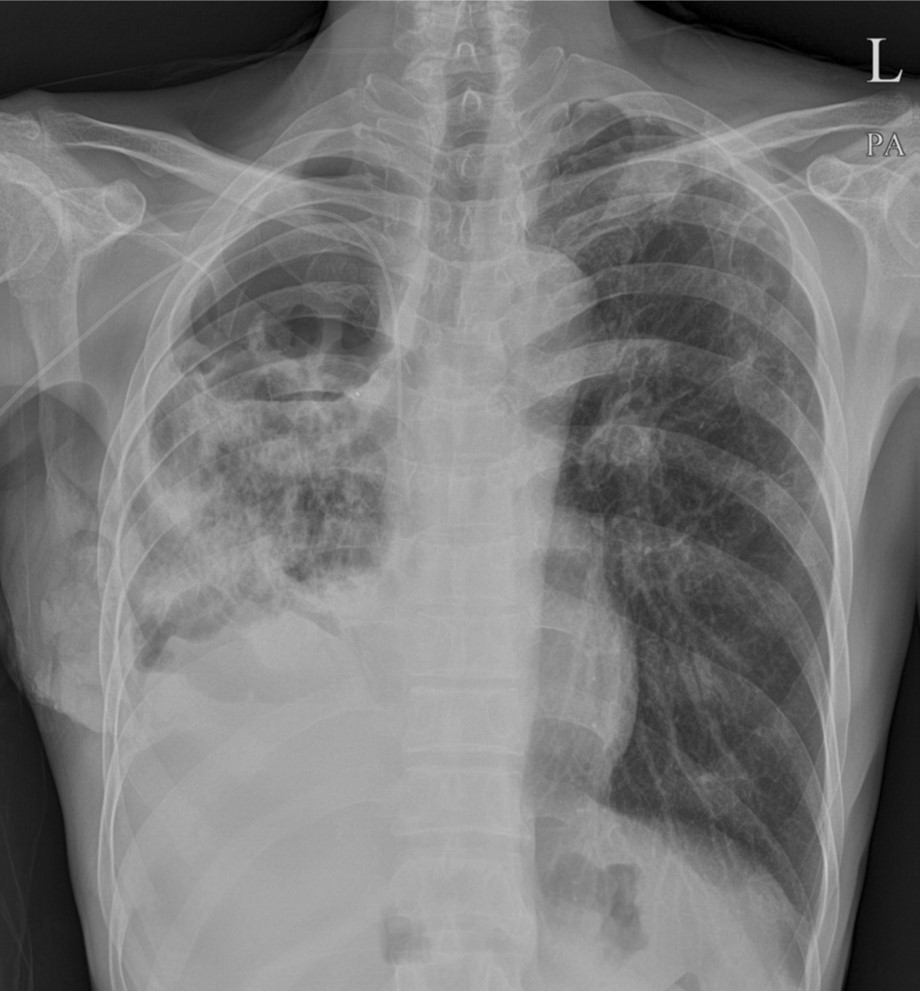

Fig. 2.

Coronal CT image shows a bronchopleural fistula between right upper lobar bronchus and deadspace.